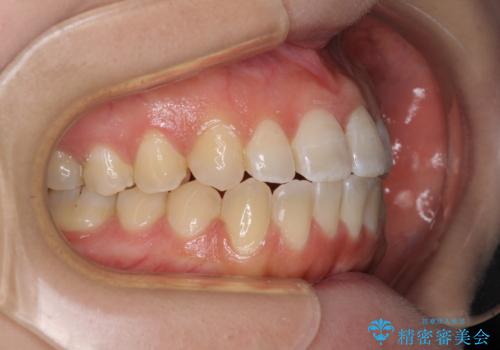

【モニター】オープンバイトをインビザラインで矯正治療

- 前歯の上下スペースによる食べにくさを気にして来院された患者様です。

インビザラインにより上下の前歯の隙間を閉じていくこととしました。

前歯のデコボコの解消と並行して上下の奥歯を圧下させるようにすることで、前歯を接触させるように計画しました。

上下の隙間に舌が入り込むことがオープンバイトの原因であったため、舌の筋肉のトレーニングも並行して行い、後戻りの抑制を図りました。